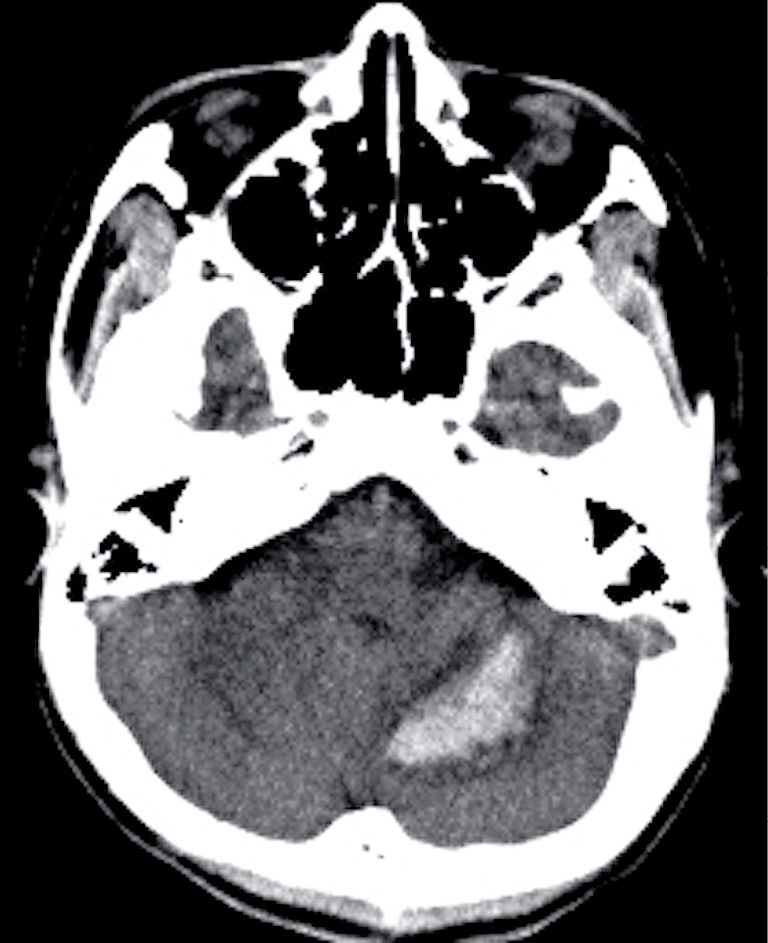

Coronavirus disease 2019 (COVID-19)-related intracranial hemorrhage (ICH) is believed to be associated with at least one known risk factor for ICH, such as hypertension, hyperlipidemia, diabetes mellitus, severe pneumonia, or anticoagulation therapy. However, in this study, we report a case of ICH in a 14-year-old boy with mild COVID-19 infection without pneumonia who had no such risk factors. The only abnormal laboratory finding was temporary depletion of vitamin K-dependent coagulation factors. This case indicates that COVID-19 infection may cause simultaneous asymptomatic intracranial microhemorrhages and temporary depletion of vitamin K-dependent coagulation factors. This temporary depletion might transform the intracranial microhemorrhages into symptomatic ICH.

与冠状病毒病 2019(COVID-19)相关的颅内出血(ICH)被认为至少与一个已知的 ICH 危险因素有关,如高血压、高脂血症、糖尿病、重症肺炎或抗凝治疗。然而,在本研究中,我们报告了一例 ICH 病例,患者是一名 14 岁男孩,患有轻度 COVID-19 感染,无肺炎,且无上述危险因素。唯一的实验室异常发现是维生素 K 依赖性凝血因子的暂时性耗竭。该病例表明,COVID-19 感染可能同时导致无症状性颅内微出血和维生素 K 依赖性凝血因子的暂时性耗竭。这种暂时性消耗可能会将颅内微出血转变为有症状的 ICH。